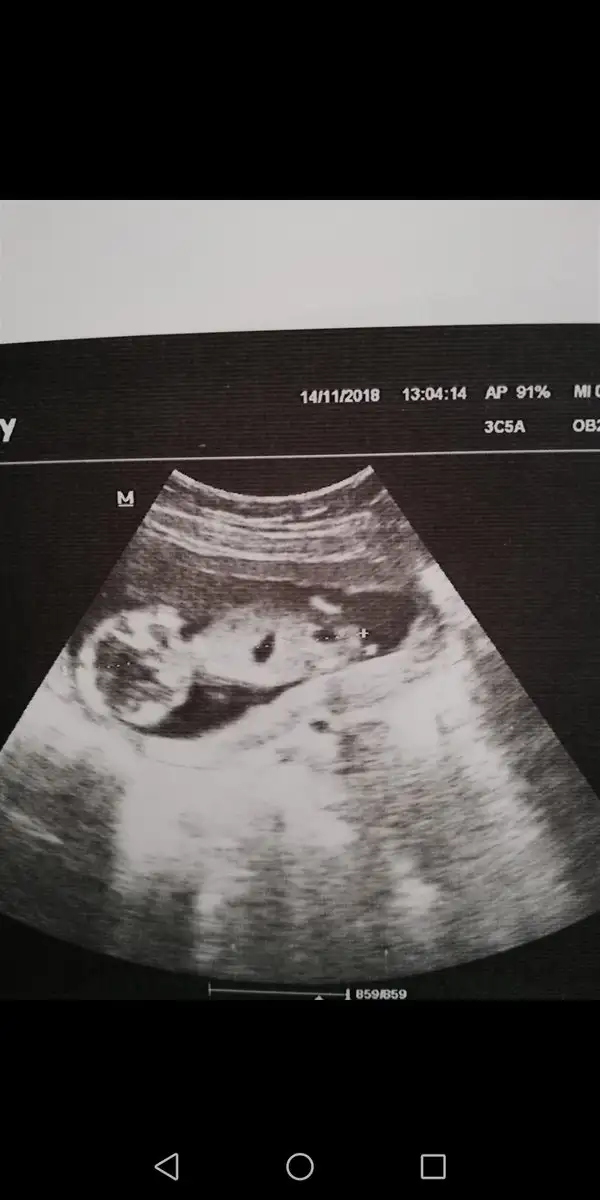

Screenshot_20181114-143434.webp

ebislerim sırtı dönmüş bir sekilde

Kendi doktorunuzla kontrol umuz 16 haftalıkken dayanamayıp başka bir doktora gittim ama oda söylemedi cinsiyet sadece hiç bişey göremedim dedi siz nubreorisine göre taumin edebiliirmsnniz canim gEki Görüntüle 2205812 ebislerim sırtı dönmüş bir sekilde

Canım ben duruş pozisyonundan dolayı nubu göremedim..